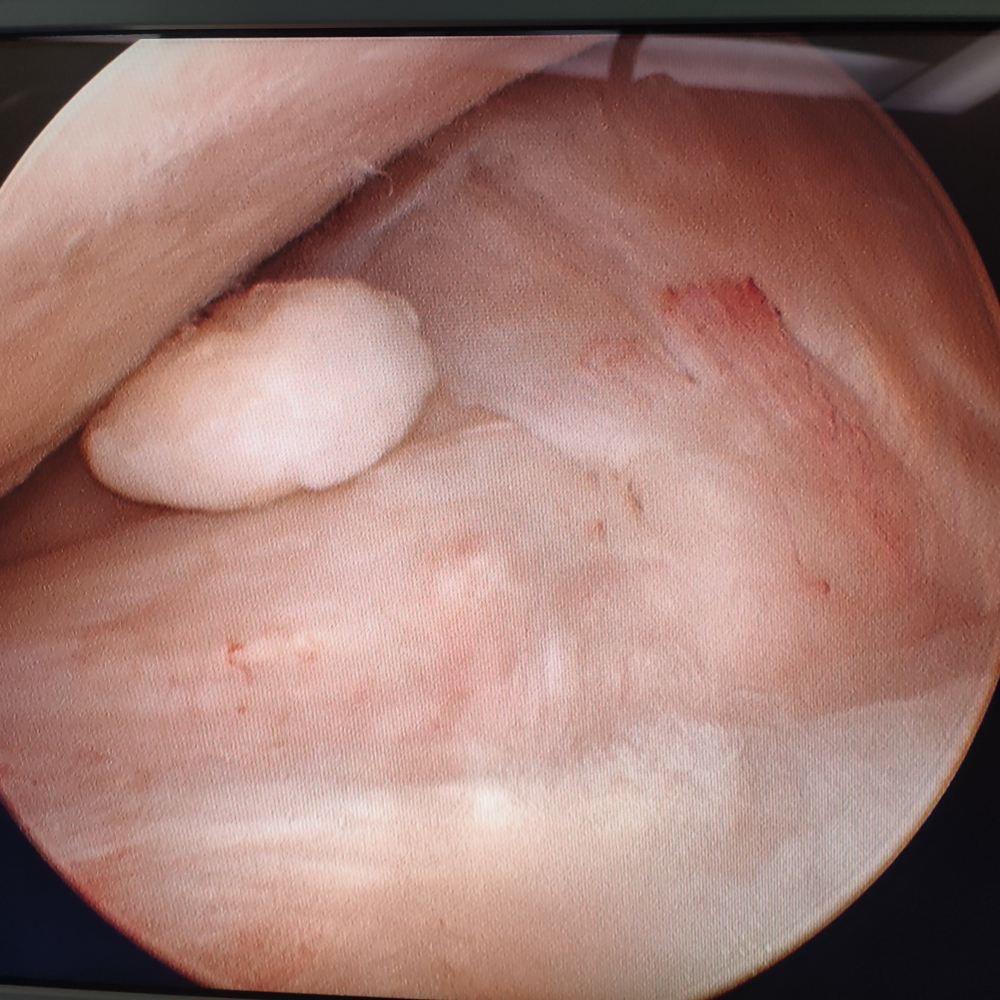

膝关节镜下发现患者膝关节游离体